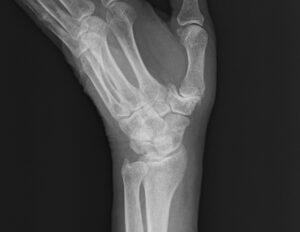

以下の5枚は再発後、手術直前に撮影されたレントゲン写真である。正面像では舟状骨遠位部に骨折線が見え、斜位像および側面像では骨片のずれが明確に確認できる。

/レントゲン写真を角度を変えて5枚撮影

第5章 手術前レントゲン

再発が判明し、紹介状を持って県内の大学病院を受診した。

そこではまず、これまでの経過とレントゲン画像が丁寧に確認された。

医師は画像を示しながら、落ち着いた口調で説明を始めた。

「舟状骨は血流が乏しいため、保存療法だけでは再び骨癒合が進まない可能性があります。

今回のように再発した場合、手術で確実に固定するほうが治癒につながりやすいと考えます。」